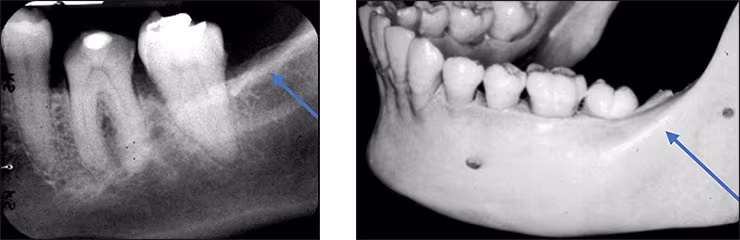

Mandibular canal – The mandibular canal is the pathway in bone where the inferior alveolar nerve and blood vessels course through the mandible. The canal extends from the mandibular foramen within the ramus anteriorly to the mental foramen (Figure 29 B). This tubular bilateral radiolucency often demonstrates fine radiopaque boundaries (Figure 29 A). The mandibular canal is recorded on mandibular premolar and molar periapical images. It is also referred to as the inferior alveolar nerve canal. The mandibular foramen is not recorded on mandibular periapical images.

Figures 29 A&B: Mandibular Canal